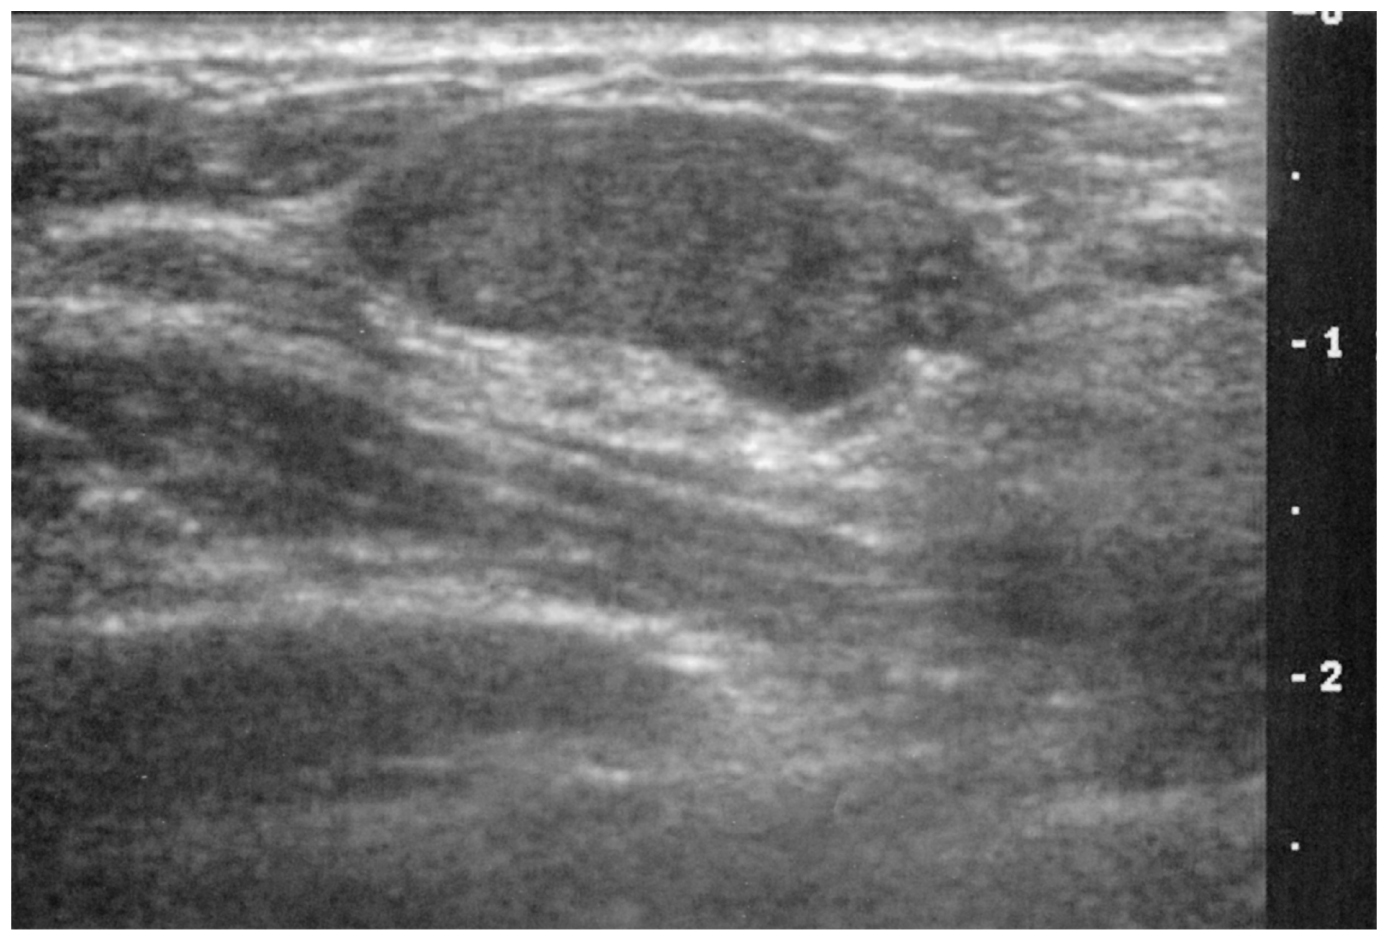

22歳の女性。右乳房のしこりを主訴に来院した。右乳房に長径約2cmの卵形の腫瘤を触知する。腫瘤は表面平滑で弾性硬,可動性は良好で圧痛を認めない。乳頭からの分泌物を認めない。乳房超音波像を下に示す。

最も考えられるのはどれか。